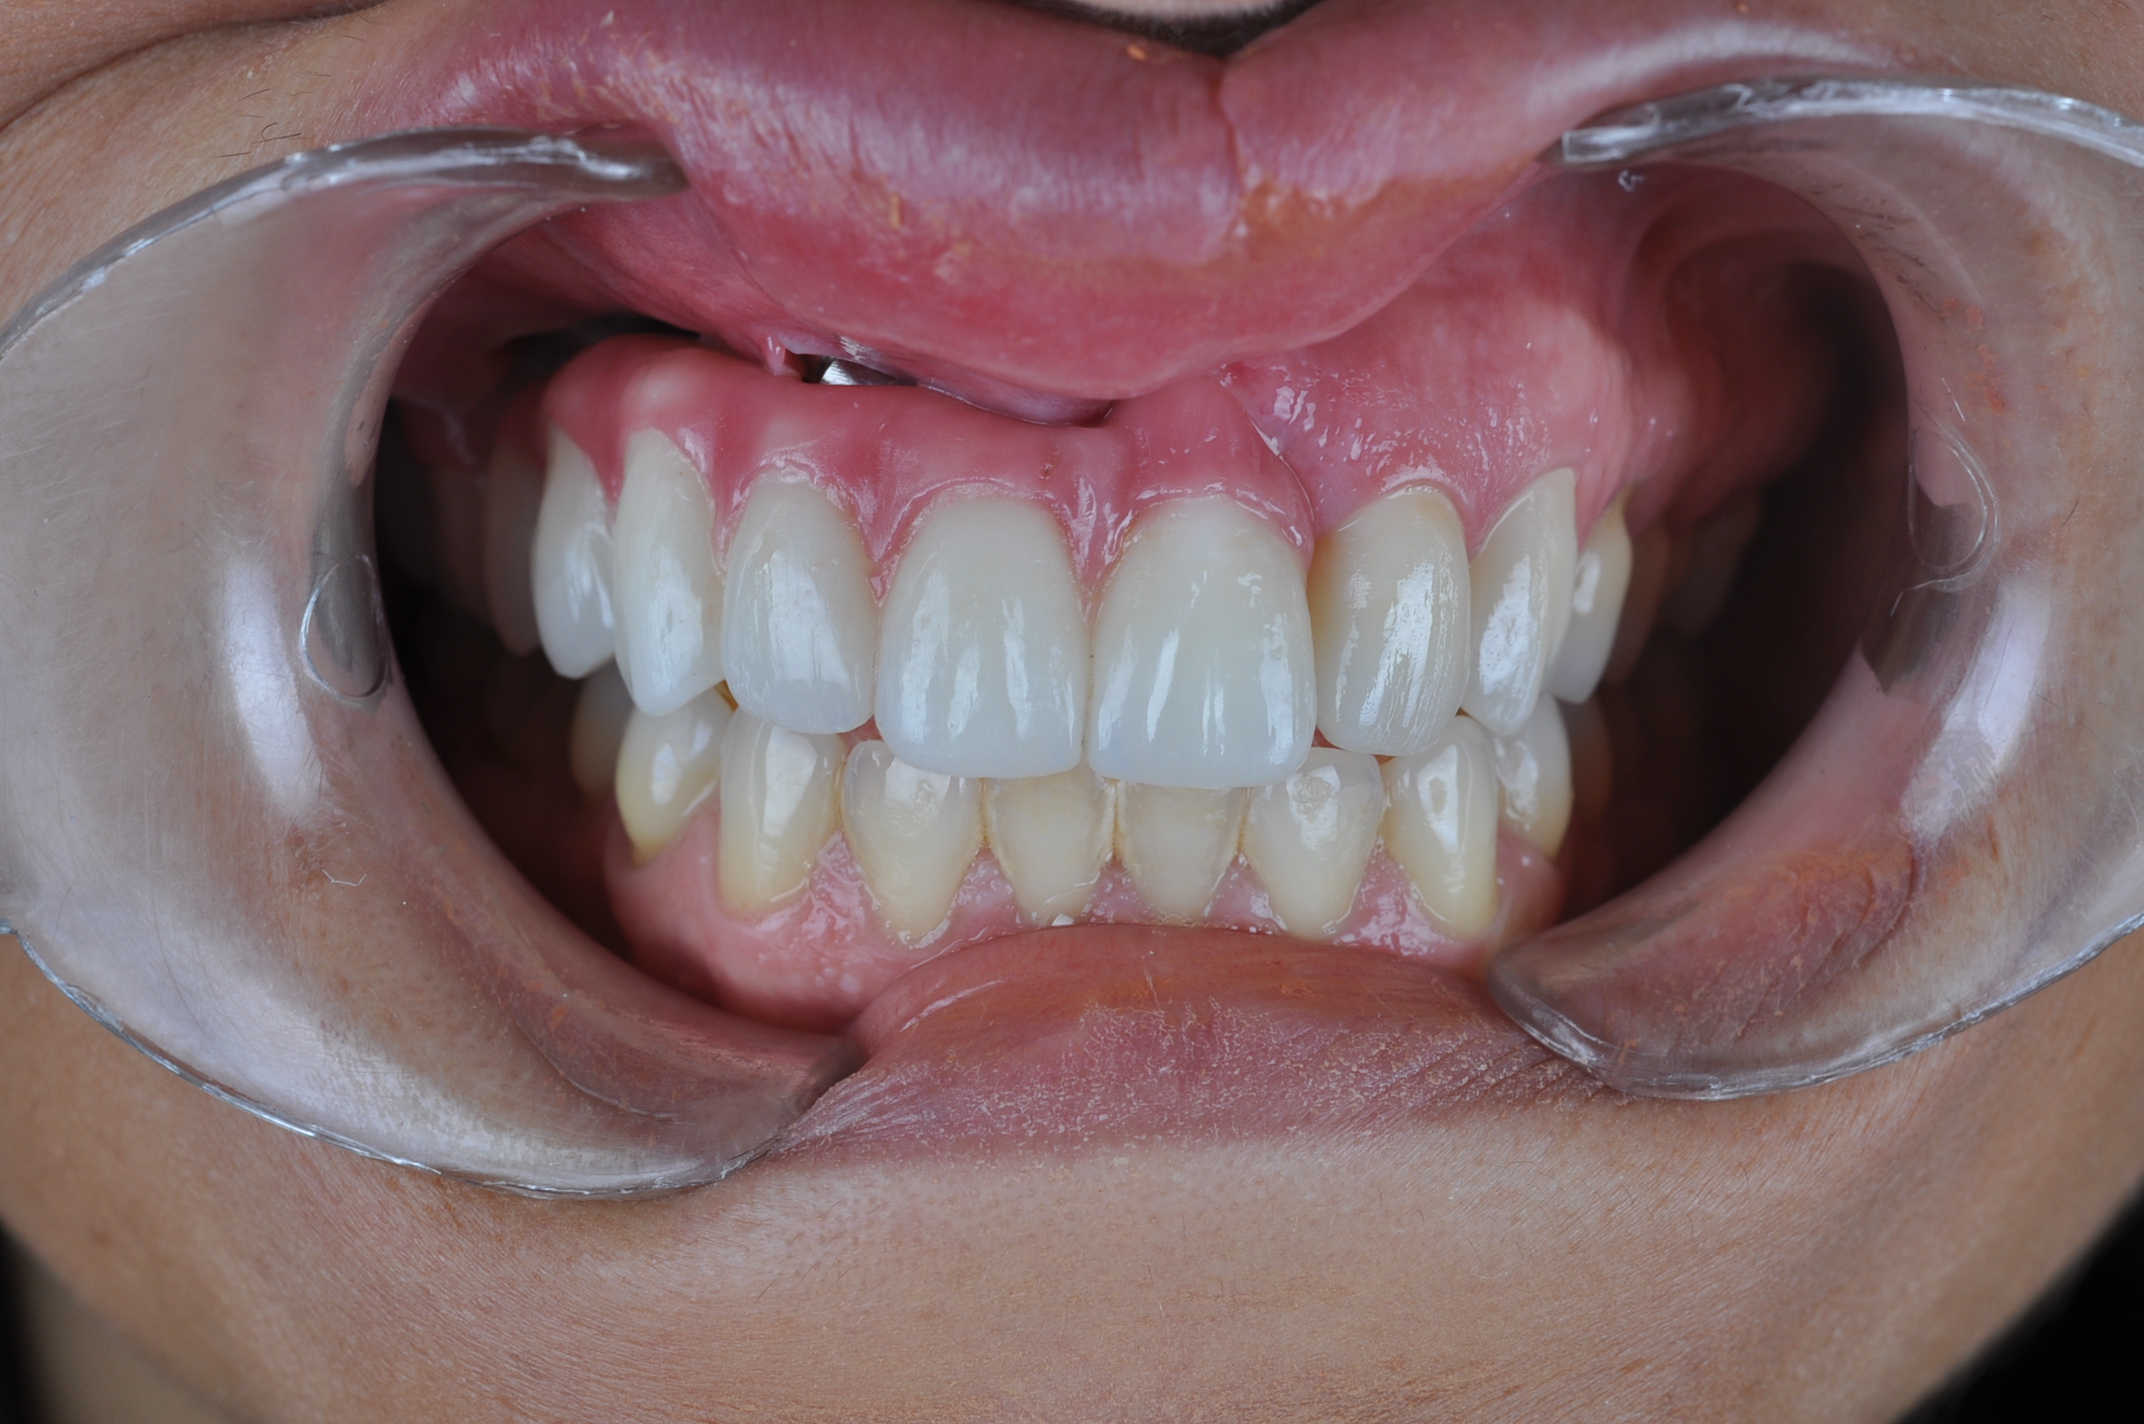

Métodos: Se llevó a cabo un caso clínico en una paciente de 40 años con fracaso de restauración fija dentosoportada en el incisivo central superior izquierdo, asociado a caries radicular subgingival con mal pronóstico restaurador. Tras la evaluación clínica y radiográfica, se indicó la exodoncia atraumática del diente afectado. Inmediatamente después, se realizó la colocación de un implante postextracción. El defecto periimplantario (gap) fue rellenado con un xenoinjerto óseo bovino. De forma simultánea, se llevó a cabo un injerto de tejido conectivo con el objetivo de optimizar el volumen y la estabilidad de los tejidos blandos periimplantarios. Se procedió a la colocación de una restauración provisional inmediata atornillada, diseñada para preservar el perfil de emergencia y guiar la cicatrización de los tejidos periimplantarios. Tras un periodo de cicatrización de cuatro meses, se colocó la restauración definitiva atornillada.

Resultados: El seguimiento clínico y radiológico evidenció una correcta osteointegración, estabilidad de los tejidos periimplantarios y un resultado estético satisfactorio, mantenido a los cuatro años.